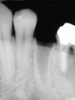

左下顎 詳細画像 (画像をクリックしてください)